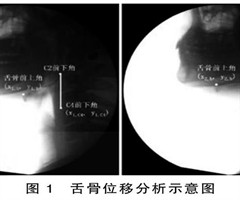

脑卒中吞咽困难病人吞咽造影特点及其对误吸的预测价值研究

摘要目的:分析脑卒中吞咽困难病人吞咽造影特点并探讨其对误吸的预防作用。方法:选取2019年1月—2022年2月于我院进行住院治疗的235例脑卒中病人作为研究对象,按照是否发生吞咽困难分为吞咽困难组(112例)和吞咽正常组(123例)。通过吞...